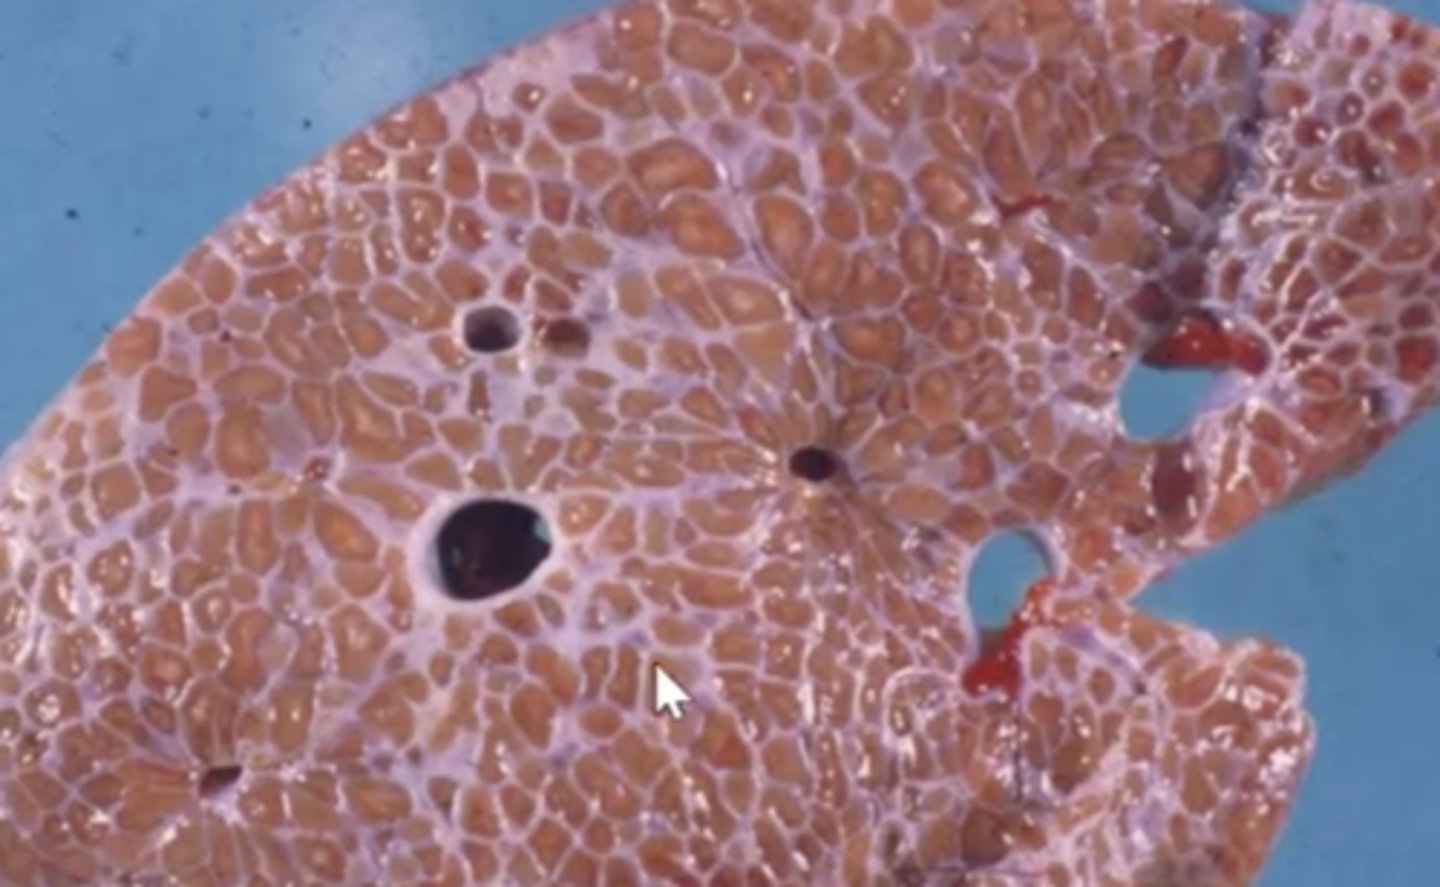

Telangiectasis (Peliosis Hepatitis)

What has caused this gross appearance of the liver?